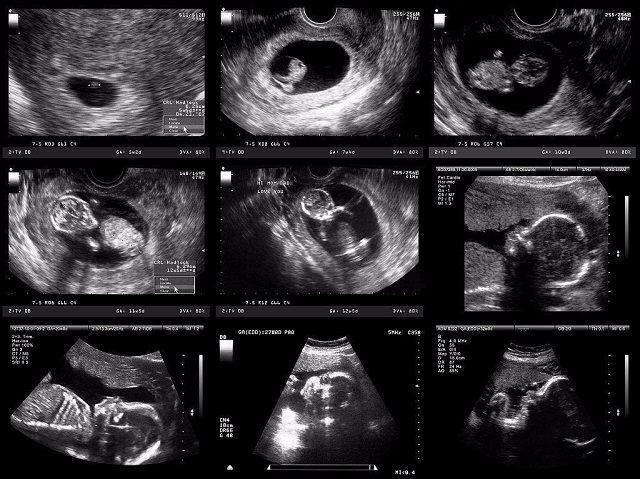

妈妈从孕育到孩子的出生,中间要经历10个月。网上有一组生动形象的动图,可以看出这十个月妈妈究竟经历了什么,这个期间,宝宝每个月在妈妈的肚子里的状态都是不一样的。如果有看过一个胎儿从开始孕育到出生10个月的不同形态,你就会感受到生命的神奇,宝宝在妈妈肚子里每个月不同的形态。

怀孕第一个月

孕妈在刚刚怀孕的时候,宝宝那会儿还只是一个胚胎,被子宫包裹住也就只有鸡蛋那么大。如果孕妈反应激烈,呕吐恶心,这个时期的孕妈是非常难受的。

怀孕第二个月

当宝宝在妈妈肚子里呆到第二个月的时候,胎儿从一个胚胎变成了雏形,而且孕妈的子宫壁也会越来越薄。

怀孕第三个月

这个时候,其实是胎儿发育最快的时期,基本上已经占满了妈妈的整个子宫。孕妈的子宫就会变得很大,还会压迫到膀胱,从这个时候开始就会有尿频的感觉,去厕所次数越来越多,而且肚子也会明显的凸出来。

怀孕第四个月

怀孕四个月的时候,孕妈会感觉到肚子胀痛或者有下坠的感觉,是因为此时的子宫正在慢慢变大,长出盆骨。

怀孕第五个月

孕妈在怀孕第五个月的时候,此时肚子就已经很大了,在肚脐眼下方很容易能够摸到子宫,此时的子宫变得很大。

怀孕第六个月

怀孕六个月时,孕妇的肚子隆起得很明显,而且子宫会挤压内脏,会让孕妈出现胸闷、呼吸不畅的一些现象。

怀孕第七个月

孕妈在怀孕第七个月的时候,孕妇吃的东西会越来越多,体重上升增幅很大,这是因为胎儿在这个时期需要吸收更多的营养来供自己成长,在这个时候最忌讳的就是孕妇节食。

怀孕第八个月

孕妈在怀孕八个月的时候,肚子会有发紧的现象,大腿和腹部会出现妊娠纹,此时孕妈的情绪不稳定,容易烦闷焦躁,睡眠严重不足。

怀孕第九个月

怀孕第九个月时,由于子宫占满了整个腹腔,所以对孕妈的食欲有很大影响,有些孕妇肚子非常大,可能会压迫到心脏,出现心悸气短的情况,而且还会有腹痛的感觉。这个时候孕妇身边不能离开照顾的人,防止出现紧急状况。

怀孕第十个月

孕妈怀孕第十个月的时候,孩子即将就要来到这个世界,孕妈在生完孩子之后子宫就会慢慢自然收缩变小。